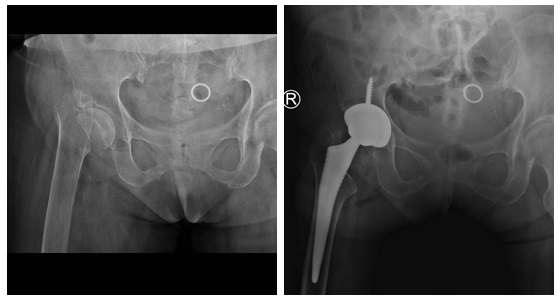

今年68岁的杨奶奶,五年前在家不慎摔倒,在当地医院检查后发现右髋股骨颈骨折并发静脉血栓,因为担心手术风险,杨奶奶在亲友的劝导下放弃手术选择保守治疗。期间,杨奶奶右髋关节疼痛难忍,只能卧床休息,不能站立行走,对她生活造成了极大的不便。一年后,由于长期卧床,杨奶奶发生一次中风,导致右侧肢体偏瘫,从此生活更加不能自理,家人照护困难。

杨奶奶入院后,周天宝主任医师组织科室医护人员认真分析患者病情,仔细阅读杨奶奶术前各种相检查结果,充分做好各项术前准备,并根据患者股骨颈骨折的特点,制定了手术方案。周天宝主任医师指出:“患者股骨颈陈旧性骨折,有全髋关节置换指征,根据患者情况需注意:1、术前伤侧肢体较健侧短缩约4cm,术中需要松解,恢复下肢等长。 2、患侧中风偏瘫,肌力差,要避免术后脱位风险。 3、患者卧床多年,骨质疏松,术中操作要预防新发骨折。 4、患者有糖尿病,术后控制血糖,预防伤口感染。5、术后康复非常重要”。

手术当日,周天宝主任医师团队与麻醉科及手术室医护人员紧密配合,顺利为患者进行右侧人工髋关节置换术。术后,杨奶奶安全返回病房。